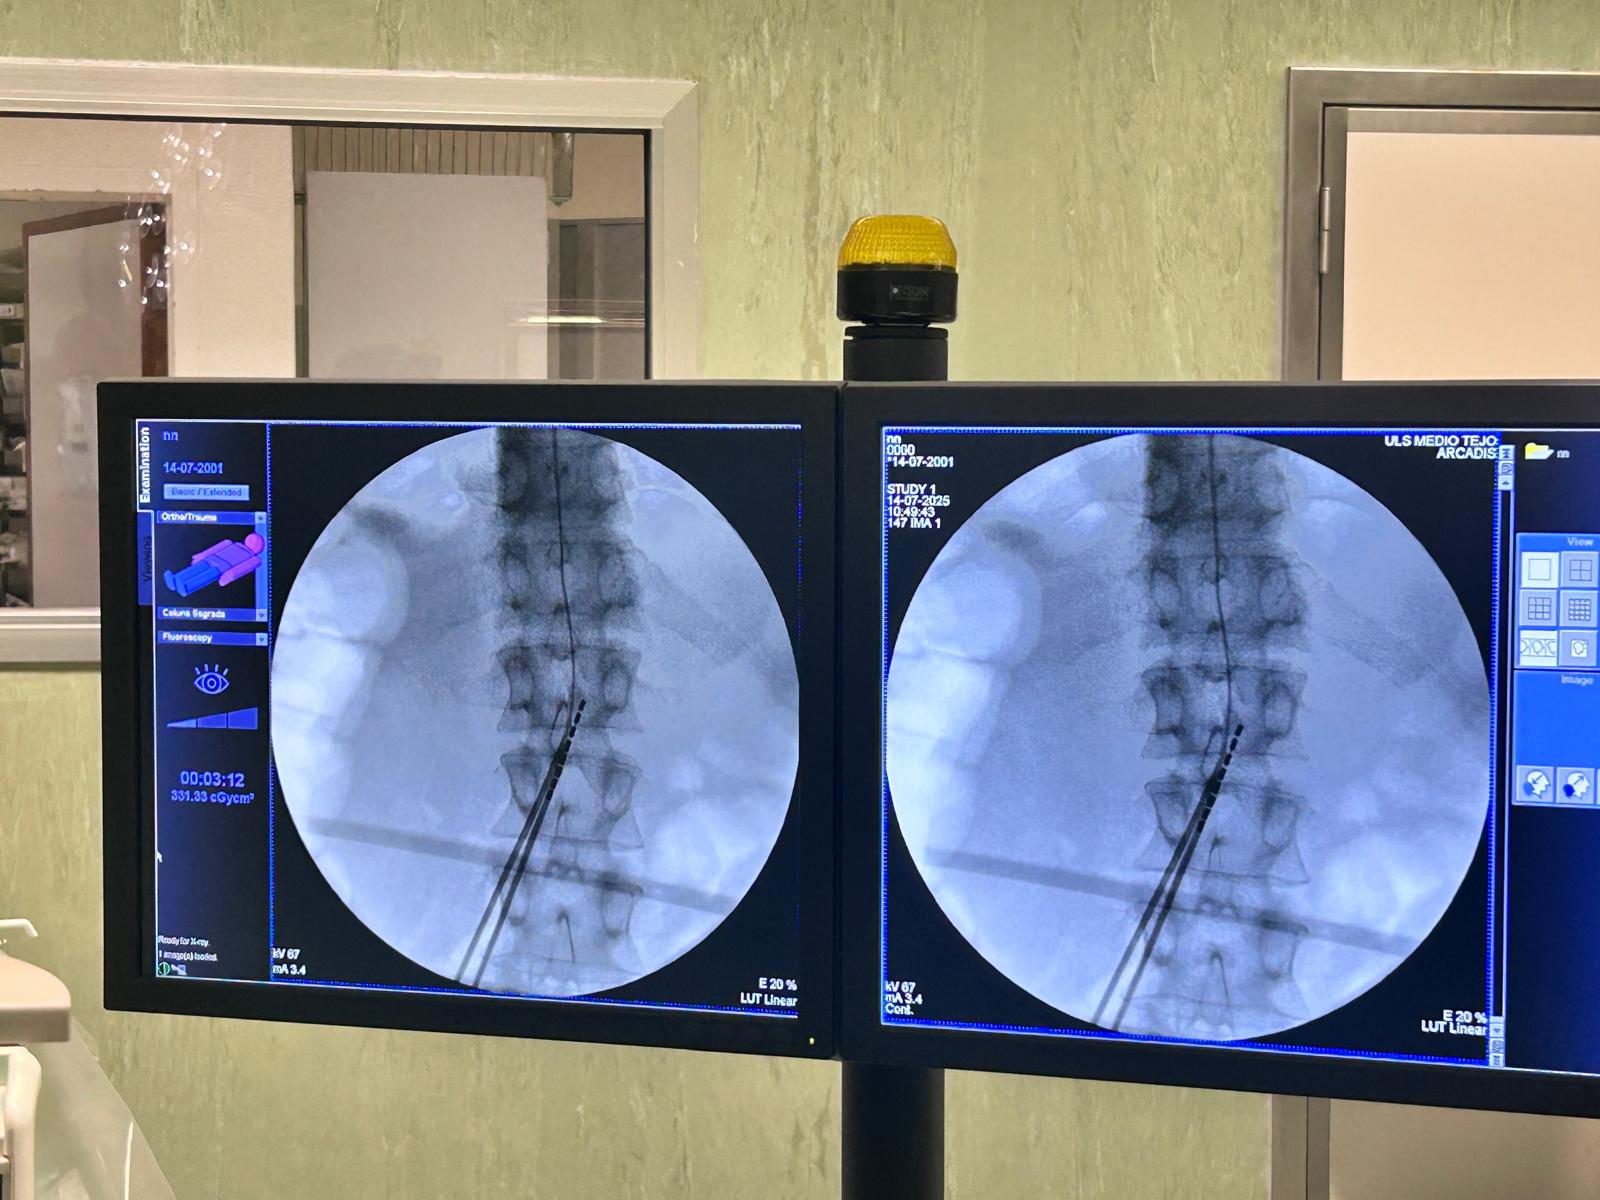

É uma novidade da área da saúde no Médio Tejo. Foi realizada pela Unidade Local de Saúde do Médio Tejo (ULS Médio Tejo), no bloco operatório do Hospital de Tomar, a colocação pioneira de um neuroestimulador medular. É a primeira vez que algo do tipo é feito na região.

Esta intervenção pioneira foi realizada num doente com síndrome de dor espinal persistente tipo 2, uma condição crónica da coluna, caracterizada por dor intensa e refratária, que permanece mesmo após cirurgia e sem complicações visíveis.

Após vários tratamentos convencionais sem sucesso, como medicação, fisioterapia, apoio psicológico e radiofrequência, foi proposto a este utente da ULS Médio Tejo um novo passo terapêutico: a implantação de um neuroestimulador medular, que se trata de um dispositivo elétrico colocado junto à medula espinhal. O equipamento em questão, envia impulsos elétricos suaves que interferem com a transmissão dos sinais de dor ao cérebro, reduzindo a sua perceção, sem provocar sensações de formigueiro associadas a terapias menos recentes.

Esta intervenção foi realizada com sucesso pelos médicos anestesiologistas Mariano Veiga, Edgar Semedo e Nuno Franco, com o suporte de uma equipa multidisciplinar composta por profissionais de enfermagem do Bloco Operatório e da Unidade de Dor, técnicos de Imagiologia e uma psicóloga clínica.